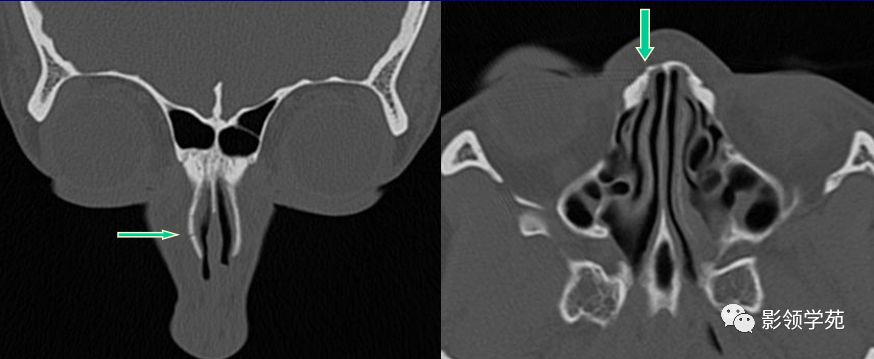

鼻骨冠状面HRCT

线性骨折 粉碎骨折

右侧鼻骨线形骨折

鼻骨线形骨折

左侧鼻骨线形骨折